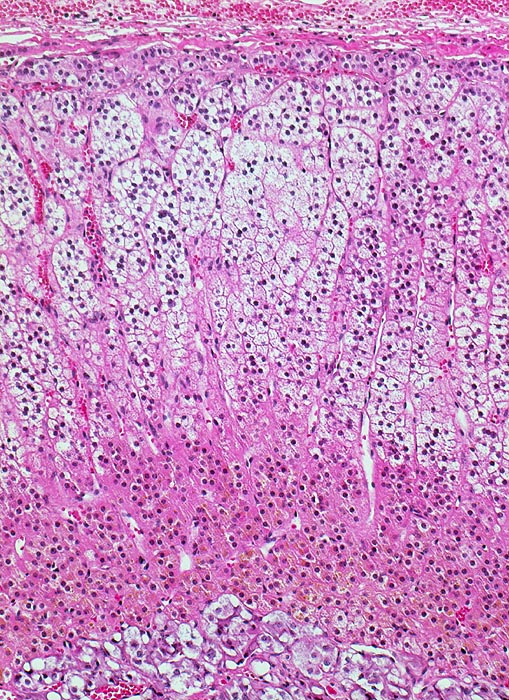

Schichten der Nebenniere von oben nach unten:

Zona glomerulosa: kleine eosinophile Zellen mit dunklem Kern; Zellnester. Bildungsort für Mineralocorticoide.

Zona fasciculata: große, helle, schaumige Zellen radiär ausgerichtete, parallele Zellsäulen. Bildungsort für Glucocorticoide.

Zona reticularis: intensiv angefärbte, kleinere Zellen; netzartige Zellstränge (eher locker); bräunliches Lipofuscinpigment. Bildungsort für Sexualhormone.

Nebennierenmark: feingranulierte, polygonale Zelle; enge Zellnester; muskelstarke, weitlumige Venen (mit Längsmuskeln); evtl. multipolare Ganglienzellen (große Zelle + großer Kern)

Das kombinierte Gewicht beider Nebennieren bei gesunden Erwachsenen Frauen und Männern beträgt ca. 8g. Die Dicke der normalen Nebennierenrinde beträgt 1mm (0.7-1.3mm).